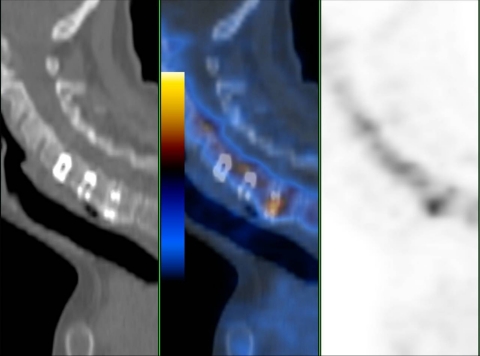

Fig. 1.

64-year-old female patient 92 months postoperatively with the lowest of three cervical cages (C4/5, C5/6, C6/7) showing increased fluoride uptake (patient no. 1). Sagittal low-dose CT, fused PET/CT, PET

Regarding cervical intercorporal fusions, there were four patients with more than one intervertebral fusions, three with two adjacent segments either both with or without increased uptake. One patient had received three adjacent intercorporal fusions of which only the lowest showed increased uptake (Figs. 1, 2, 3).